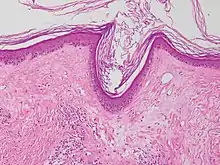

Interface dermatitis with lichenoid inflammation

| Generally/Not otherwise specified | Typical findings:[2]

| Lichen planus | Irregular epidermal hyperplasia with a jagged “sawtooth” appearance, compact hyperkeratosis or orthokeratosis, foci of wedge-shaped hypergranulosis, basilar vacuolar degeneration, slight spongiosis in the spinous layer, and squamatization. The dermal papillae between the elongated rete ridges are frequently dome shaped. Necrotic keratinocytes can be observed in the basal layer of the epidermis and at the dermal-epidermal junction. Eosinophilic remnants of anucleate apoptotic basal cells may also be found in the dermis and are referred to as “colloid or civatte bodies”. Whickham striae are usually seen in the areas of hypergranulosis. Vacuolar degeneration at the basal layer may be noted leading to focal subepidermal clefts (Max Joseph spaces). Squamatization occurs as a result of maturation and flattening of cells in the basal layer. It happens in areas of marked hypergranulosis with prominence of the sawtooth pattern of rete ridges. Wedge-shaped hypergranulosis can occur in the eccrine ducts (acrosyringia) or hair follicles (acrotrichia). In the hypertrophic subtype, the associated hyperkeratosis, parakeratosis, hypergranulosis, papillomatosis, acanthosis, and hyperplasia markedly increased with thicker collagen bundles forming in the dermis. Moreover, the rete ridges are more elongated and rounded as opposed to the typical sawtooth pattern. In atrophic LP, loss of the rete ridges and dermal fibrosis is prominent. In vesiculobullous LP, the disease progression is quicker. Hence, some of the distinctive features such as hyperkeratosis, hypergranulosis, or dense lymphocytic dermal-epidermal infiltrate may not be present. LP lesion may resolve with residual hyperpigmentation caused by a persistent increase in the number of melanophages in the papillary dermis.[9] |  |  |